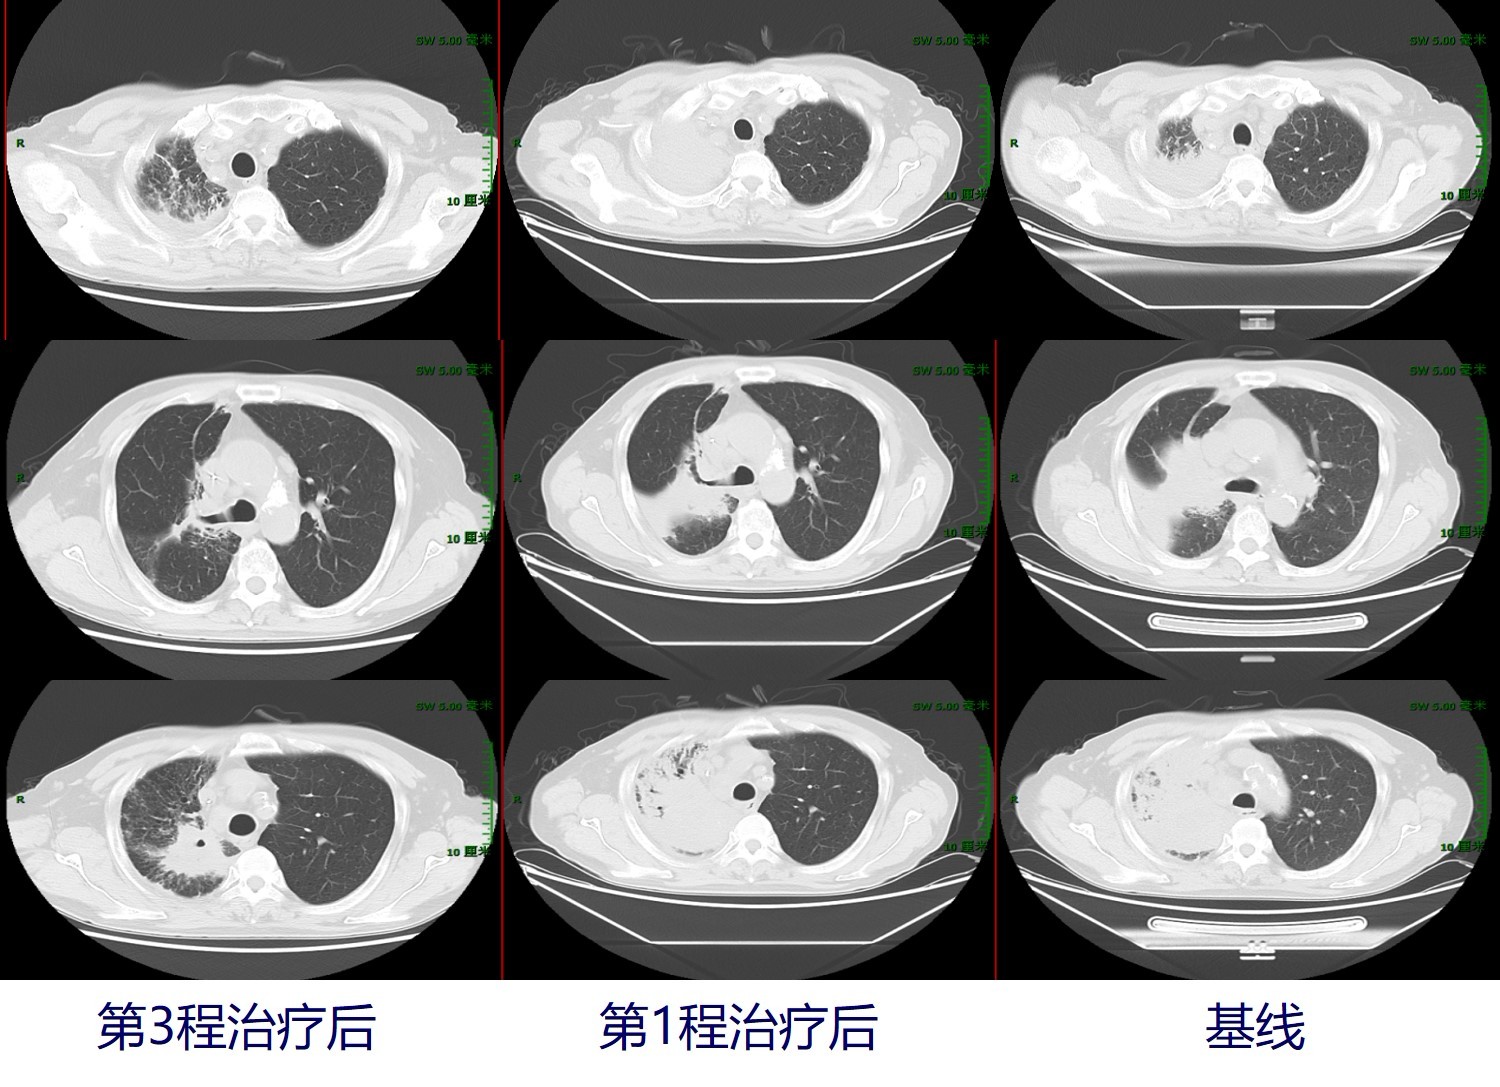

分别于2019年7月11日、2019年8月9日接受第2和第3程减量治疗,具体方案为:信迪利单抗(达伯舒)200mgd1+紫杉醇135mg/m2 d1+DDP 20mg/m2 d1-3(q21d)。治疗后副反应:化疗后不适,体重稳定,血象无异常。2019年8月31日行胸部CT检查示:右肺上叶占位(4.3cm*3.8cm)伴右肺上叶支气管截断、右肺上叶阻塞性改变,纵隔淋巴结肿大:较前(2019年7月9日)右肺上叶渗出实变有所吸收,右肺下叶斑片渗出有所吸收。头颅MRI增强:左侧额叶转移瘤(4mm),较2019年6月13日明显缩小,病灶周围水肿不明显。综合评估患者治疗后的疗效情况,外周血肿瘤标志物下降,见下图1。疗效评估显示:第1次免疫联合化疗后,疗效评价为SD;第3次免疫联合化疗后,疗效评价为PR。

图2. 治疗过程中的肺部病灶变化:肿瘤明显缩小